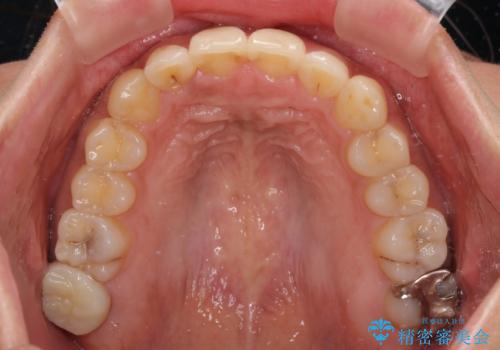

【モニター】歯列が狭くデコボコが気になる 急速拡大装置を用いたインビザライン矯正

矯正治療後には土台のままとなっている歯をセラミッククラウンにて補綴治療を行うこととしました。

上下の骨幅を改善したことで、スムーズに歯列矯正を行うことができました。

土台のまま放置されていた歯は土台の状態で咬み合っていましたが、急速拡大を行った際に咬み合わせが著しく挙上されたため、その際に土台を大きくすることで咬み合う歯との距離を確保しました。